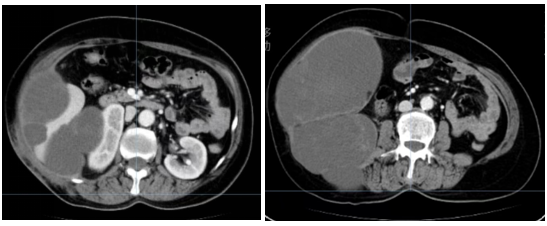

治疗前影像检查显示,肿瘤沿右侧腹腔腹壁生长并融合,形成约22×13厘米的巨大肿块,包绕并压迫肝脏、肾脏等重要脏器,且紧邻小肠。由于多形性脂肪肉瘤对化疗及常规放疗均不敏感,患者已无法再次手术切除,后续治疗陷入困境。经骨软组织多学科讨论,团队一致认为可尝试放疗干预。

患者先后完成2次空间分割放疗及14次大分割放疗后,腹腔和腹壁肿块逐渐缩小,腰部疼痛完全缓解。放疗结束后3月复查CT显示,原腹腔巨大肿瘤明显消退,仅残留少量低密度软组织影,对肝、肾及小肠的压迫完全解除,腹腔结构及脏器形态基本恢复正常。